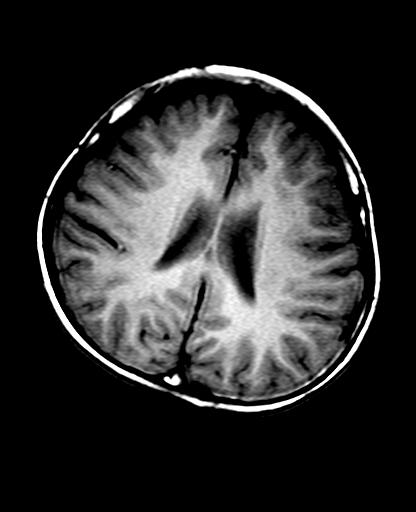

头痛10天、间断呕吐2天。f 6岁

入科化验血清铜及铜兰蛋白均减低,脑脊液正常,血清神经原烯醇化酶明显增高。wbc:5.94x109/l、

临床表现及实验室检查符合肝豆状核变性

mri未见明显异常。但临床支持考虑肝豆状核变性。